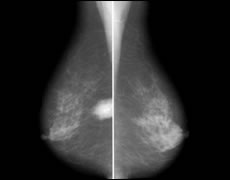

マンモグラフィ

微細な石灰化(非腫瘍性)を映し出すことができます。

触ってもわからない初期の乳がんを発見できるX線検査です。

※女性の罹患率トップは乳がんです

| 2方向撮影 | 5,580円(税込) |